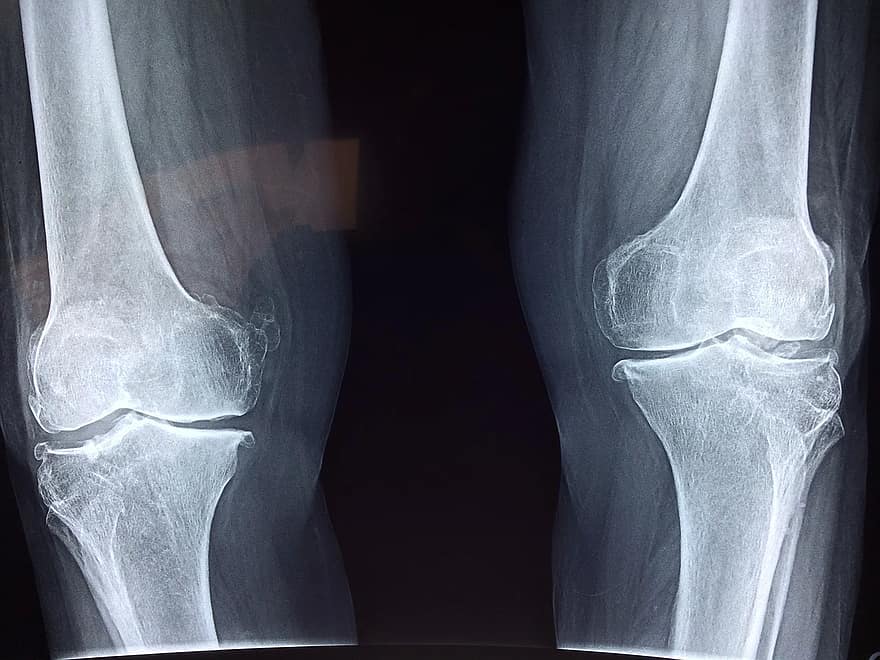

무릎 골관절염

무릎 골관절염이 있을 때도 발 보조기 처방으로 도움이 됩니다. 발 보조기는 지면 반발력에 영향을 주고 무릎관절 같은 근위부 관절에 영향을 미치게 됩니다. 무릎관절의 내측이 좁아진 형태를 보이는 골관절염에 발 보조기 사용으로 외측 발뒤꿈치 쐐기를 사용할 수 있습니다.

발 뛰꿈치 쐐기의 두께는 0.5cm 정도로 뒤꿈치 외측면에서부터 내측으로 점차 얇아지는 형태로 제작합니다. 경증 무릎 골관절염 환자의 경우에는 통증의 완화로 증상 호전을 보이는 경우가 흔하고 내측 관절 공간이 완전히 사라진 심한 무릎 관절염 환자에서도 통증이 완화된다는 보고도 많이 있습니다. 이러한 쌔기를 사용하면 보행기저가 넓어지게 됩니다.